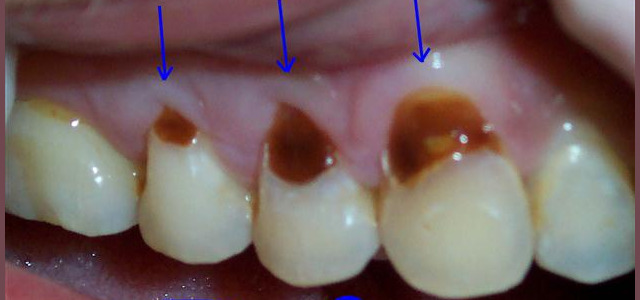

Restorative Dentistry

Restorative dentistry services focus on repairing teeth damaged to cavities, tooth decay, or trauma. From our beginning, it has been our goal to help our patients restore strength and structure to their smiles. We are committed to helping your smile stay beautiful and healthy for a lifetime. We incorporate the latest dental technology to ensure you receive the most advanced care. Our restorative services include:

Crowns

Dental Bonding

Composite Fillings